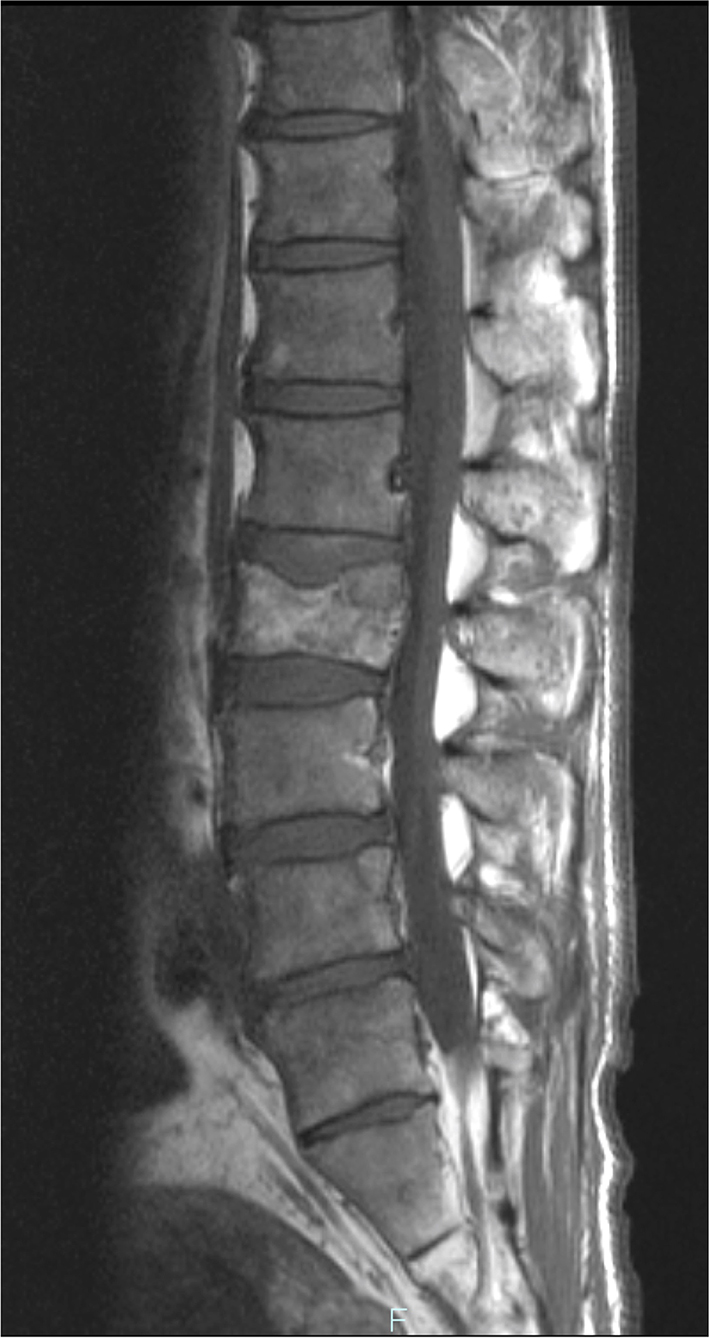

The blood test showed liver dysfunction and pre-renal dehydration. The circulating white blood cells were 13,440 cells/mL, hemoglobin was 12.4 g/dL and the platelet count was 27.8 × 104 cells/μL. The chemistry panel showed a potassium level of 5.1 mmol/L, chloride of 99 mmol/L, phosphate of 3.6 mg/dL and elevated levels of lactate dehydrogenase (LDH), aspartate aminotransferase (AST), alanine aminotransferase (ALT), alkaline phosphatase (ALP), total bilirubin (TB), direct bilirubin (DB) and C-reactive protein (CRP). Computed tomography and MRI revealed disseminated metastatic changes in lumbar spinal (Fig. 1), well-defined pulmonary tumors in the right lower and left upper lobes (Fig. 2) and an ambiguously bordered low-density area of the liver, predominantly in the left lobe as well as a moderate volume of ascites (Fig. 3).

![]() Click for large image | Figure 1. Spinal MRI. T1-weighed MR image showed metastatic lesions spread widely in the vertebral bodies. |